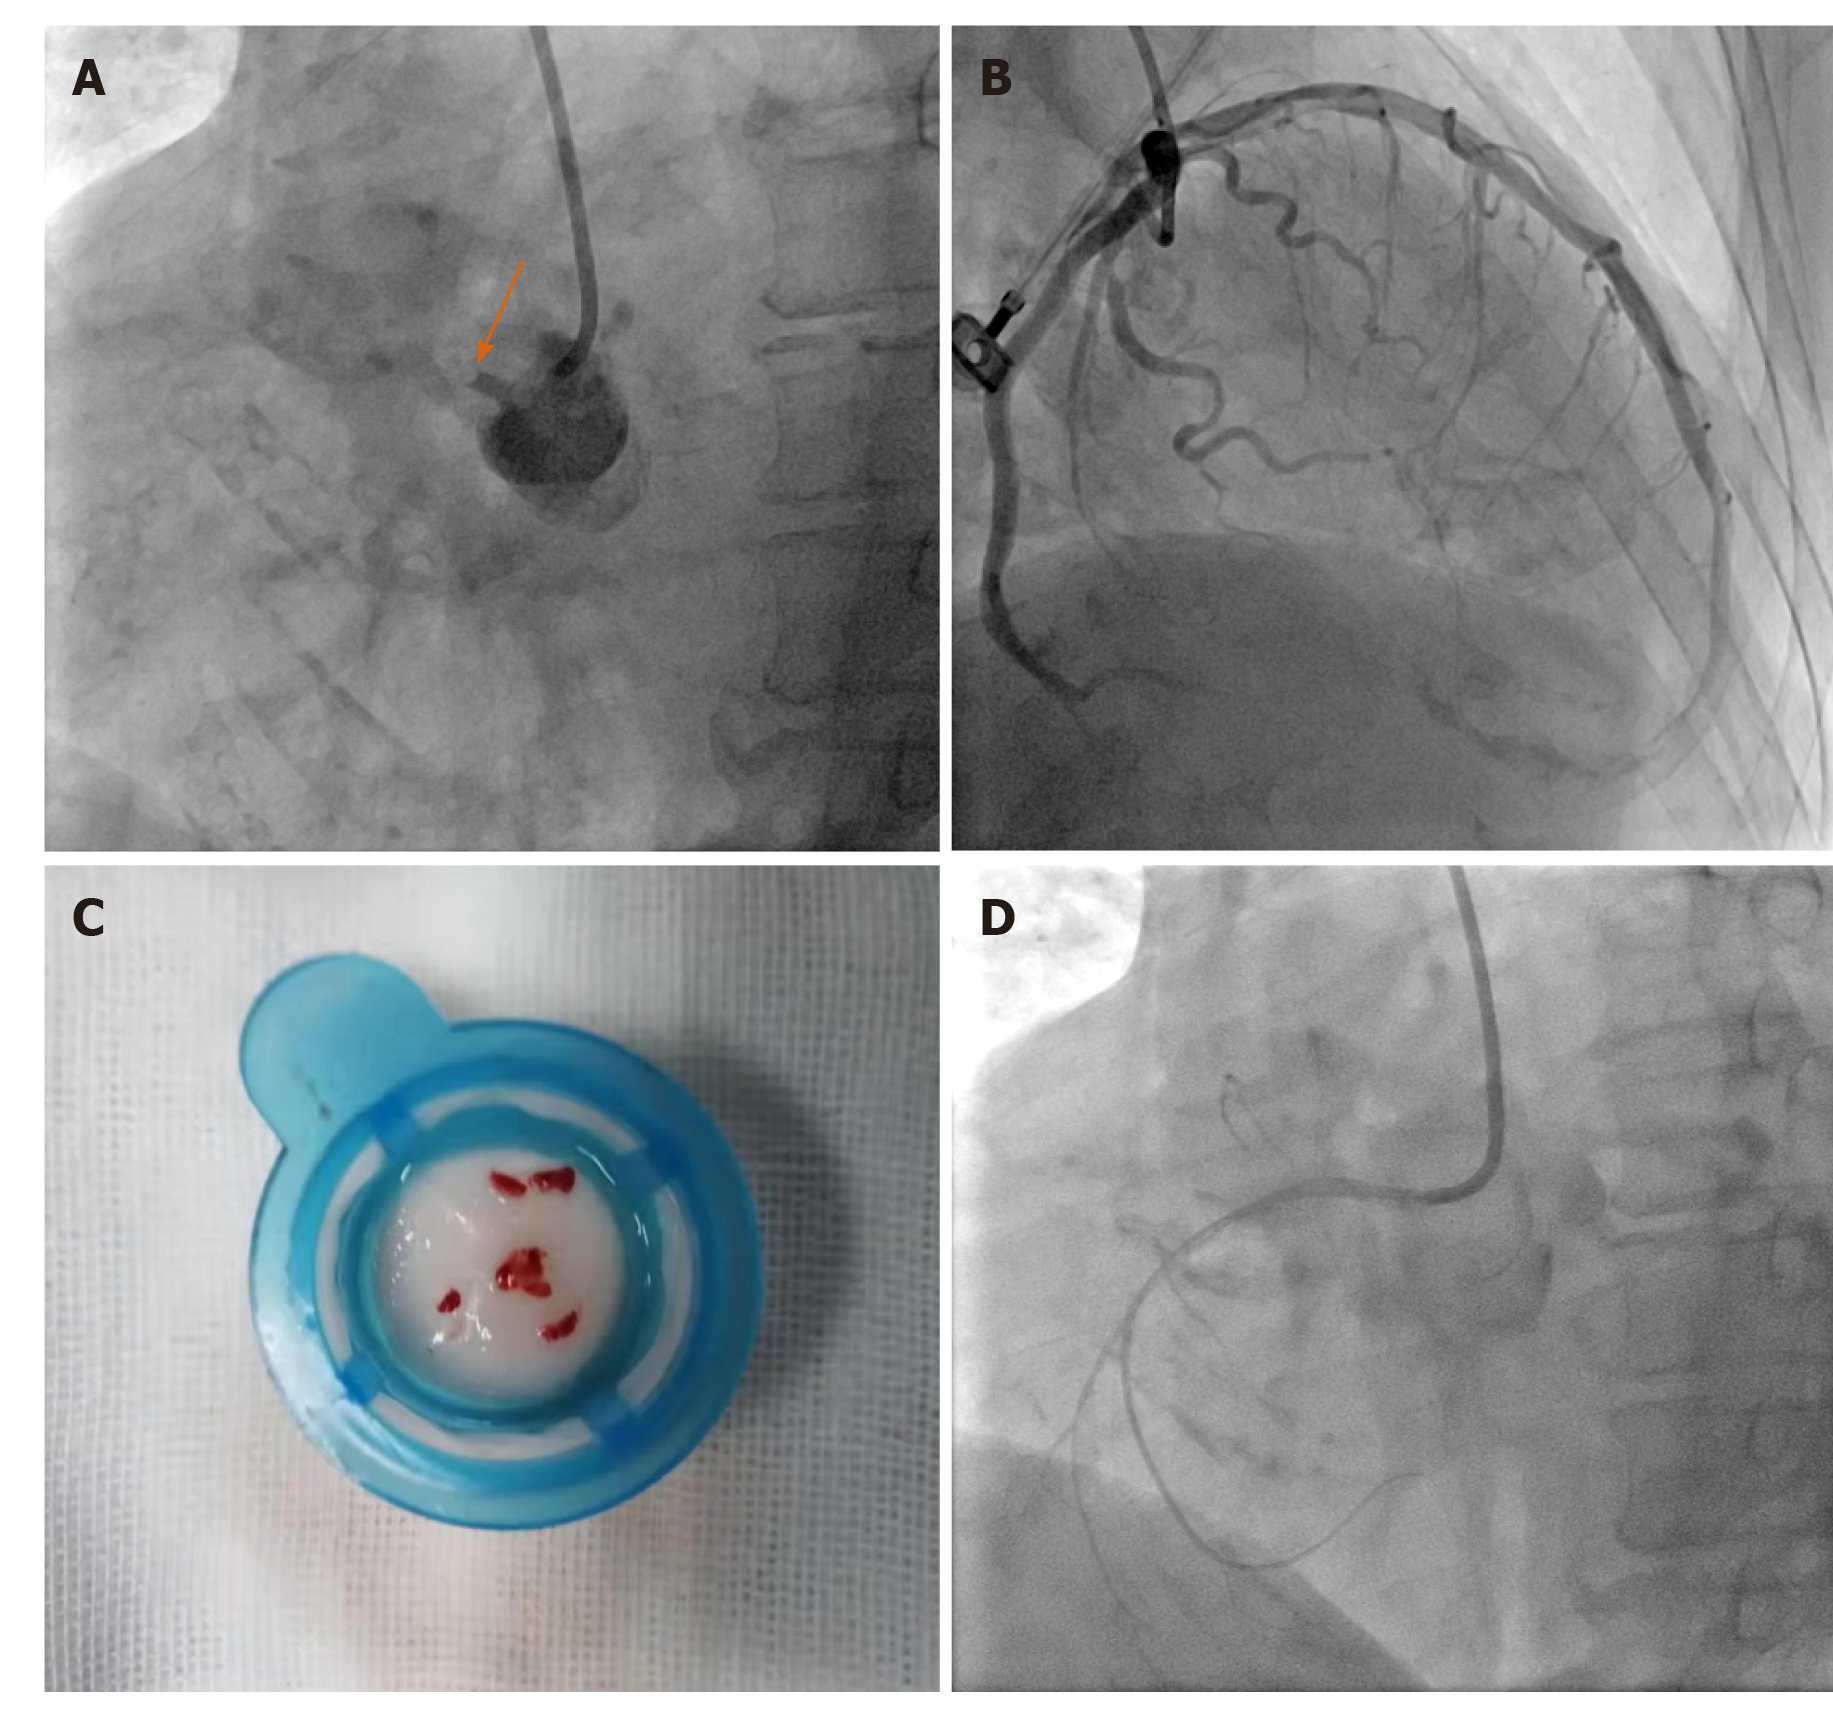

Coronary angiogram: showing left circumflex coronary arteries tumor …

(A) A solitary mass was noted arising from the omentum. There was no …

Anomalous origin of left circumflex artery from the right pulmonary …

Computed tomography. Huge left circumflex artery to right atrium …